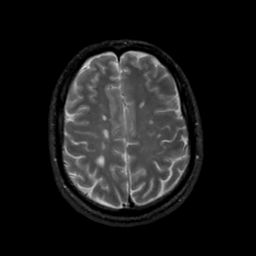

MR Study #20 October 6, 1991 -- Slice #37

[Home][Help][Clinical][Tour 1][Tour 2] Slice 37